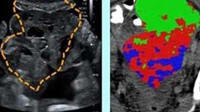

The system merges two types of imaging: line-field confocal optical coherence tomography (LC-OCT), which captures high-resolution images of skin tissue at the cellular level, and confocal Raman microspectroscopy, which analyzes the chemical makeup of specific areas identified in those images. Together, these tools allow researchers to not only see the shape and structure of cancerous cells but also understand their molecular characteristics.

The AI model performed well, achieving a classification accuracy of 95 percent for basal cell carcinoma and 92 percent when both types of cancer were included. These results suggest the system can reliably distinguish cancerous structures based on their chemical signatures. Further analysis revealed distinct chemical differences between various cancer types, offering new insights into how these cancers develop and behave. This dual-imaging approach could lead to more precise, less-invasive skin cancer diagnostics in the future. (Image credit: M. Ayadh et al., doi 10.1117/1.JBO.30.7.076008)